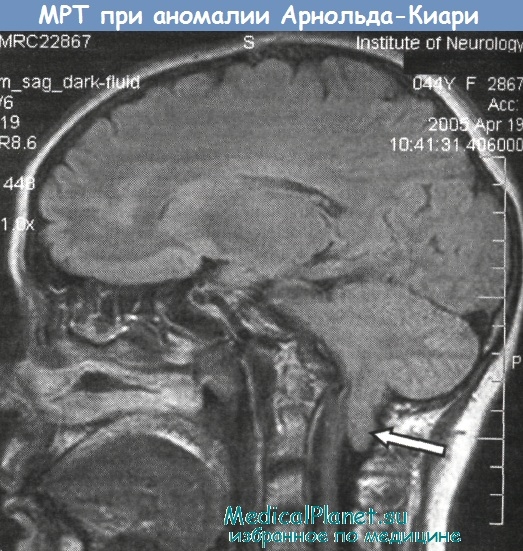

Аномалия Арнольда-Киари: MRI снимки